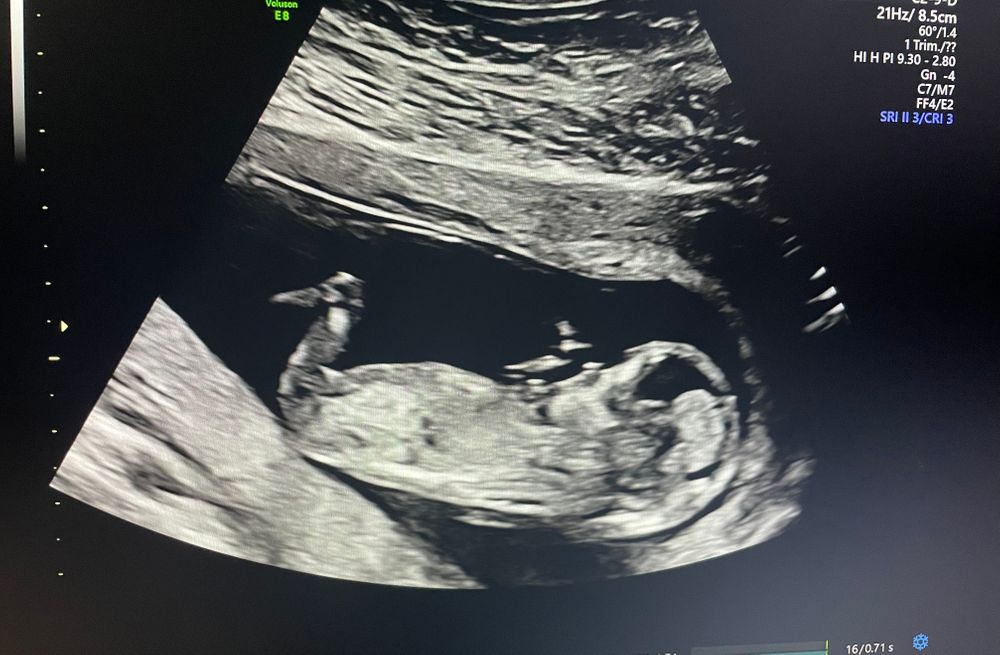

На узи увидела малыша нашего долгожданного, сосет пальчик, толкается, выгибает спинку, ручку по-царски вытянул и складывается картина, будто лежит на пляже🙈 КТР 67 мм, ЧСС 150, но долго не слушала, просто зафиксировала, вес ~65 гр, воротниковая зона 1,6 мм, носик есть и очень похож на пуговку❤️ По крови все риски <1, здоров! На пару денёчков опережает срок